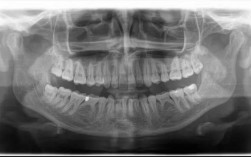

若溃疡继发细菌感染(如化脓、周围淋巴结肿大),可口服抗生素:

(图片来源网络,侵删)- 阿莫西林:广谱青霉素类,对革兰氏阳性菌效果好,成人每次0.5g,每日3次,过敏者禁用。

- 甲硝唑:针对厌氧菌(如口腔常见厌氧菌),成人每次0.4g,每日3次,服药期间禁酒,避免双硫仑样反应。

- 头孢克肟:三代头孢菌素,对耐药菌有效,但需确认无头孢过敏史。

注意:抗生素需足量足疗程使用,一般3-5天,症状缓解后停药,避免滥用导致耐药性。